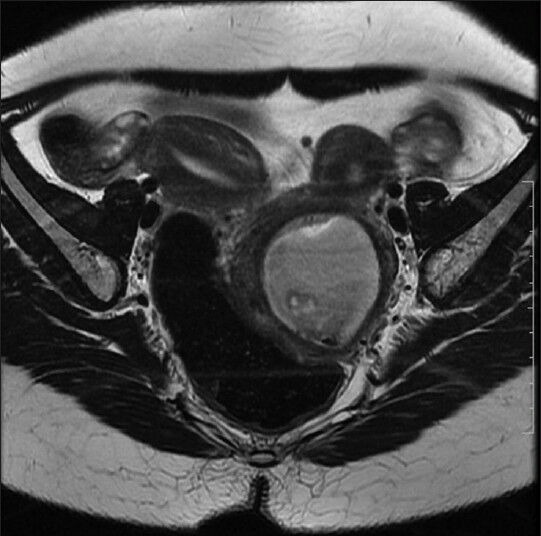

Obstructive mullerian anomalies give rise to a spectrum of clinical presentations and are uncommon in routine gynecologic practice. The patient usually becomes symptomatic in early reproductive years. Recurrent pelvic pain, dysmenorrhea, enlarging abdominopelvic mass, and abnormal vaginal discharge are the common presenting symptoms. We describe a rare case of a mullerian anomaly getting diagnosed 13 years after attaining menarche during the evaluation of postabortal sepsis. Patient presented 2 weeks following evacuation carried out for missed abortion, with acute abdominal pain, fever and foul smelling discharge per vaginum. The anomaly was identified as uterus didelphys with obstructed left hemivagina and ipsilateral renal agenesis (Herlyn-Werner-Wunderlich syndrome) complicated by pyocolpos. She was successfully managed by single-stage transvaginal septum resection under laparoscopic control.

Abstract Image